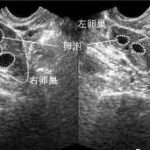

女性卵泡成熟后,专家会将一根细长的特殊取卵针固定在B超探头上,在B超的检测下,借助取卵针从阴道进入卵巢,穿刺成熟的卵泡,取出卵子。与此同时,男性也要进行取精。